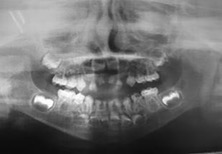

Figura 3: Radiografía panorámica año 2007

El examen clínico intraoral reveló alteración de la estructura y color de las piezas primarias, atrición y pérdida de la dimensión vertical (Figura 2). Radiográficamente se observó la presencia de coronas con marcada constricción cervical y raíces cortas (Figura 3). Presentaba alto riesgo cariogénico, por la presencia de lesiones de caries activas y dos restos radiculares, sumado a la anomalía estructural de la dentina (riesgo biológico específico) y bajo riesgo gingivoperiodontal. El riesgo socio-económico era alto por provenir de una familia con marcadas limitaciones económicas. Luego de la anamnesis, examen clínico y radiográfico, e interconsulta con el médico de cabecera se estableció el diagnóstico de DI Tipo I asociado a OI tipo I. Se planificó un tratamiento integral y preventivo con los objetivos de devolver forma y función, y proteger y evitar el desgaste de los tejidos conductas que pudieran interferir con el tratamiento.

En la radiografía panorámica de control del año 2015 se observó la progresiva obliteración del conducto radicular en el grupo incisivo superior e inferior y en los primeros molares permanentes; presentado los premolares en erupción, un conducto radicular anormalmente amplio en toda su longitud (Figura 8). En la del año 2018 se visualizó la continua aposición de dentina a nivel radicular que obliteró en forma casi total los conductos de la mayoría de las piezas dentarias, a excepción de los segundos molares inferiores (Figura 10).